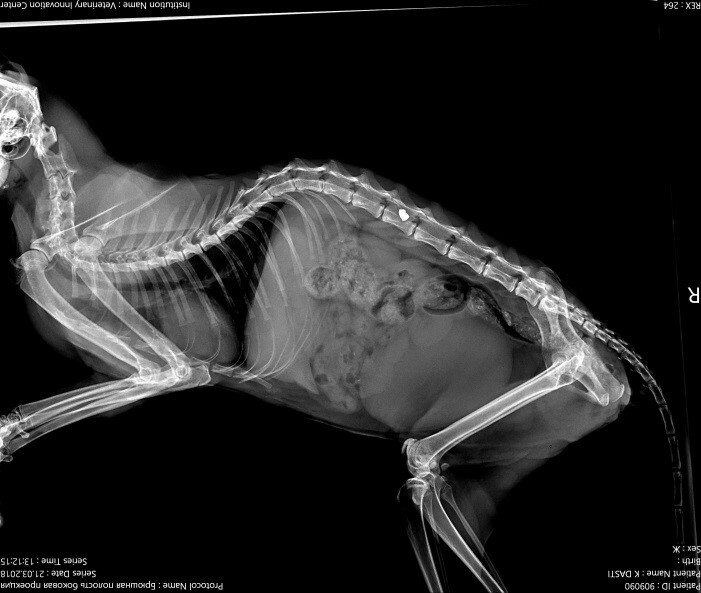

Рентгенограмма в латеро - латеральной и дорсовентральной проекции кошки, получившей пулевое ранение пневматическим оружием в область позвоночника.